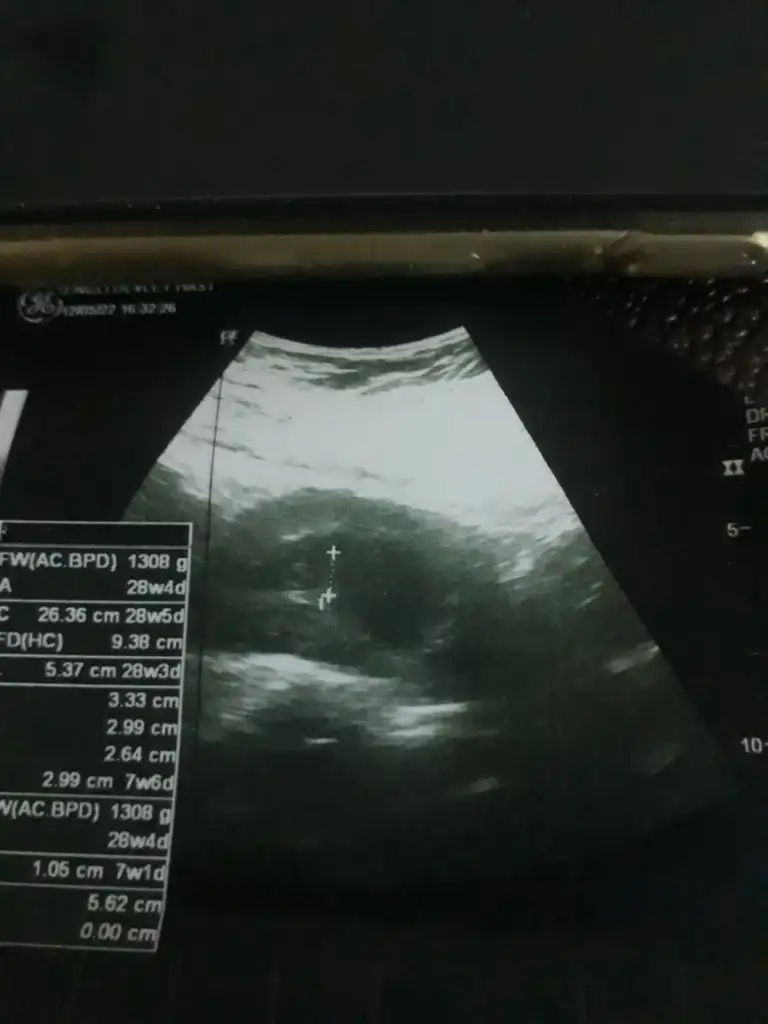

kızlar karından sağda kız solda ise erkekEki Görüntüle 3069851